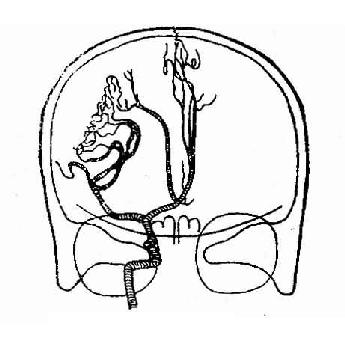

2.脑室造影改变

(1)凡位于一侧大脑半球肿瘤,常使脑室系统中线结构(透明中隔,三脑室及导水管)向对侧移位。对侧侧脑室扩大。根据肿瘤所在部位,患侧侧脑室可发生不同形式的压缩变窄和移位,甚至完全闭塞。贴近脑室的肿瘤早期即可使脑室发生局部受压变形(图2-26,27)。

大脑各区占位透明隔和第三脑室移位关系

图2-26 大脑各区占位透明隔和第三脑室移位关系

(2)第三脑室、中脑及松果体肿瘤的主要改变为两侧脑室发生对称性扩大,移位不显著,同时有全部或部分第三脑室狭窄变形。

(3)后颅凹肿瘤除使两侧脑室对称性扩大外,第三脑室也扩大,中脑导水管及第四脑室可发生移位、变形或闭塞等。